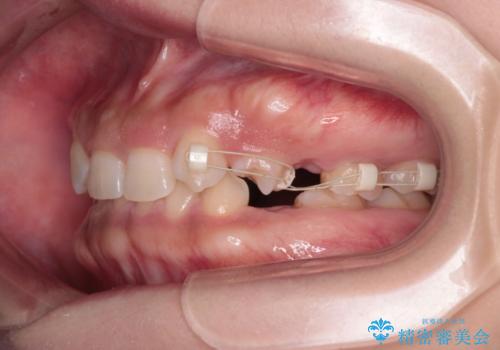

- 後続永久歯が欠損した患者様です。

矯正治療にて歯並びを改善したのち、インプラントにて咬合回復を行う治療計画としました。

捻転が強い部分だけはワイヤーの部分矯正で対応しております。